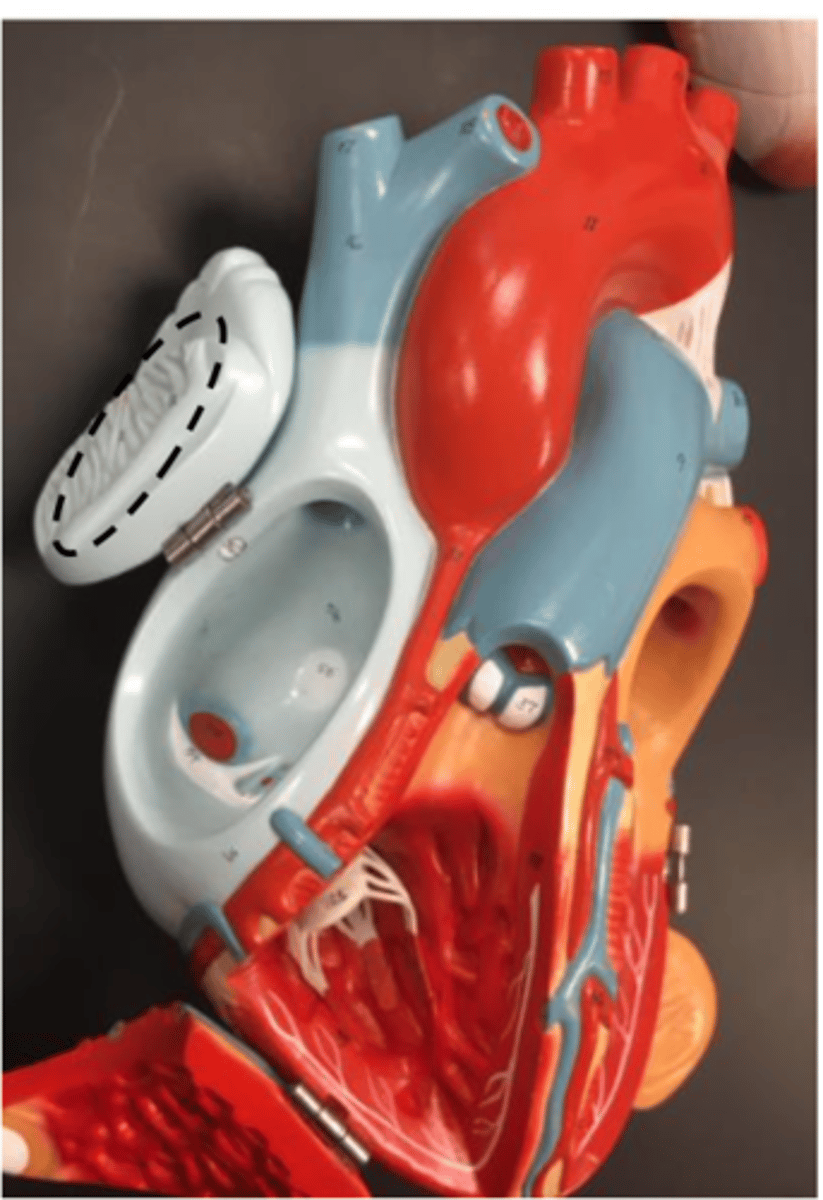

pectinate muscle

found on the auricle of the right and left atrium wall

<p>found on the auricle of the right and left atrium wall</p>